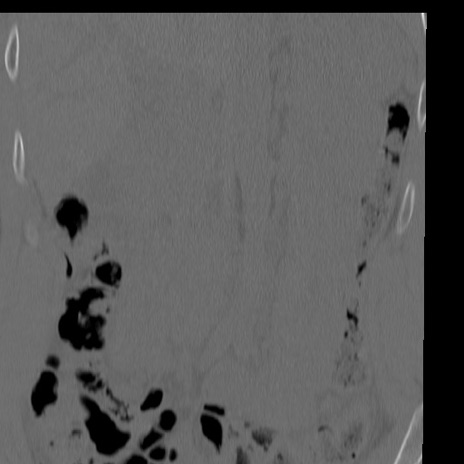

症例3 腰椎CT(冠状断像)

腰椎CT